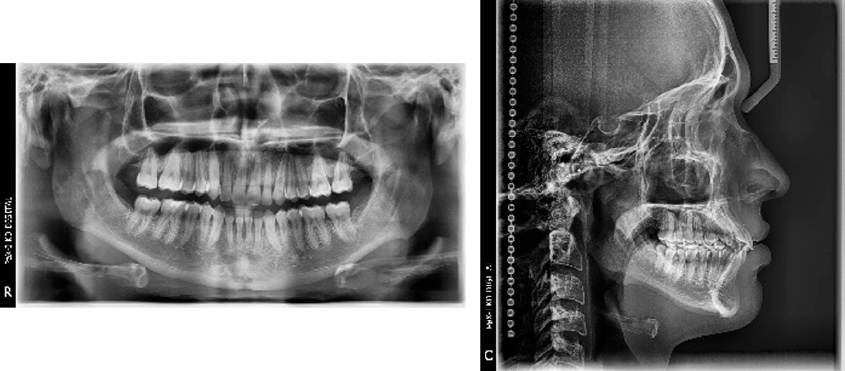

Se utilizó la siguiente secuencia de arcos durante el tratamiento: fase inicial arcos NiTi 0.014", NiTi 0.018", Thermal NiTi 0.016" x 0.022", Thermal NiTi 0.017" x 0.025"; fase de trabajo Thermal NiTi 0.019" x 0.025", acero Inoxidable 0.019" x 0.025"; finalización multitrenzado inferior 0.019" x 0.025" acero Inoxidable superior 0.019" x 0.025" y elásticos de asentamiento "N" invertida 3/16" 2 Oz. de canino inferior a canino superior, primer premolar inferior y primer premolar superior de ambos lados, elástico en "M" V/ 2 Oz de segundo premolar inferior a segundo premolar superior, primer molar inferior, primer molar superior, segundo molar inferior de ambos lados. Se retiró la aparatología fija con pinzas quita Brackets y se eliminó el exceso de resina con pinzas con punta de titanio y posteriormente con fresa multi-hoja de alta velocidad con irrigación y pulido con discos soflex. Se colocó retenedor removible circunferencial superior y retenedor fijo inferior de 3 a 3 elaborado con alambre respond 0.017". Por último, se realizó toma de ortopantomografía y lateral de cráneo (Figura 5) y sobreimposición cefalométrica (Figura 6).

Al finalizar el tratamiento de ortodoncia se observaron cambios favorables que concuerdan con los objetivos planteados al inicio del tratamiento. Clínicamente se observó retroclinación de los incisivos superiores, aumento de la sobremordida vertical, se conservó la clase I molar bilateral y se logró clase I canina bilateral. Hubo corrección del apiñamiento leve y corrección de rotaciones; los cambios de tejido blando que se observaron fueron retrusión de labio superior e inferior, y se observó escalón labial recto (Figura 7). Esqueléticamente hubo disminución de 1° del ángulo SNA, mientras que el ángulo SNB se mantuvo sin cambios. El ángulo interincisal aumentó, lo cual indica que hubo una retroclinación considerable. El ángulo del incisivo superior respecto al plano palatino disminuyó, indicándonos una retroclinación del mismo. De igual manera, el ángulo del incisivo inferior respecto al plano mandibular también mostró retroclinación al final del tratamiento (Tabla 1).